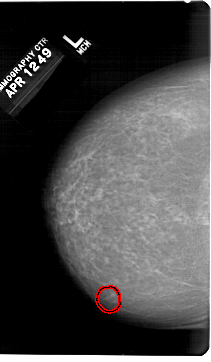

FILE: A_1307_1.LEFT_CC.OVERLAY

TOTAL_ABNORMALITIES 1

ABNORMALITY 1

LESION_TYPE CALCIFICATION TYPE PLEOMORPHIC DISTRIBUTION CLUSTERED

ASSESSMENT 4

SUBTLETY 4

PATHOLOGY BENIGN

TOTAL_OUTLINES 1

LEFT_CC LINES 6871 PIXELS_PER_LINE 4006 BITS_PER_PIXEL 12 RESOLUTION 43.5 OVERLAY